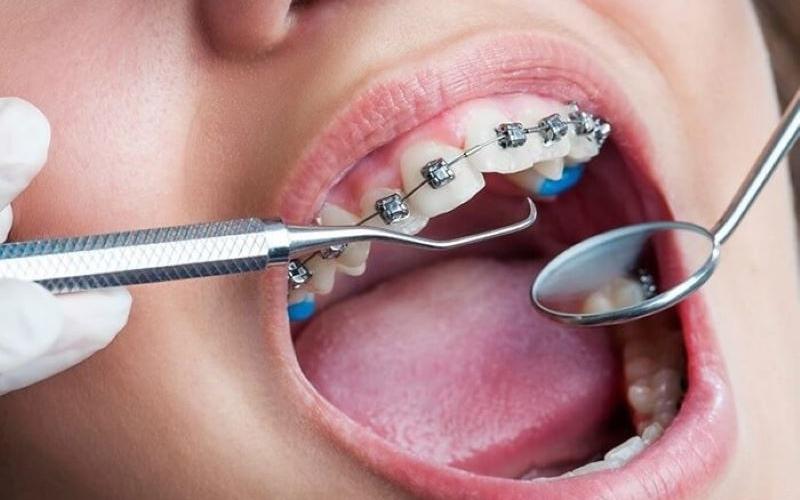

Dây cung niềng răng là một bộ phận trọng yếu trong hệ thống chỉnh nha, đóng vai trò kết nối các mắc cài với nhau và tạo lực giúp răng dịch chuyển. Có thể hình dung mắc cài giống như “cái giá đỡ” gắn trên bề mặt răng, còn dây cung chính là “đường ray” định hướng cho các răng di chuyển dần dần về đúng vị trí. Nếu thiếu dây cung, toàn bộ hệ thống niềng răng sẽ không thể phát huy hiệu quả.

Trong nha khoa hiện đại, dây cung niềng răng được sản xuất bằng những hợp kim chuyên biệt, thường là thép không gỉ hoặc hợp kim Niken – Titanium. Những vật liệu này vừa có độ cứng chắc để giữ lực, vừa có tính đàn hồi để đảm bảo sự dịch chuyển của răng diễn ra một cách từ từ, không gây tổn thương đến nướu và xương hàm. Nhờ đó, bệnh nhân có thể niềng răng an toàn trong thời gian dài mà không lo ảnh hưởng đến sức khỏe răng miệng.

Cấu tạo của dây cung niềng răng bao gồm phần lõi kim loại hoặc hợp kim, được uốn cong theo hình dáng cung hàm. Tùy vào từng giai đoạn chỉnh nha, bác sĩ sẽ lựa chọn dây cung có kích thước mảnh hay dày, độ cứng thấp hay cao. Giai đoạn đầu thường dùng dây mảnh, mềm để răng làm quen và di chuyển nhẹ nhàng. Khi răng đã ổn định hơn, dây dày và cứng sẽ được thay thế để siết mạnh hơn, giúp khớp cắn chuẩn xác.

Vai trò của dây cung niềng răng rất quan trọng. Nó chính là yếu tố tạo lực kéo, duy trì áp lực liên tục lên răng để từng chiếc răng dịch chuyển theo lộ trình. Bác sĩ chỉnh nha ví dây cung như “động cơ” của cả hệ thống niềng. Nếu mắc cài chỉ giữ cố định trên răng, thì dây cung mới là bộ phận giúp toàn bộ hàm răng thay đổi. Chính vì vậy, chất lượng và cách sử dụng dây cung có ảnh hưởng trực tiếp đến tốc độ và kết quả của cả quá trình chỉnh nha.